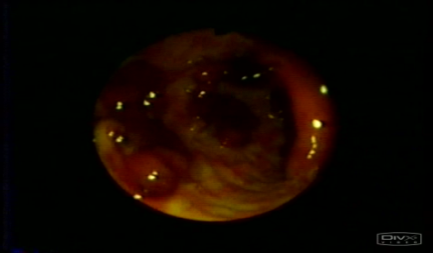

• Kolonoskopiyada kütlə

• Biopsiyada bəd xassəli törəmə

• Kolonoskopiyada polip

yob img 23